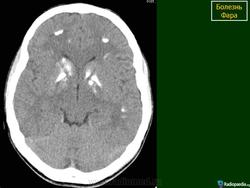

Основным методом прижизненной диагностики болезни Фара является КТ мозга, выявляющая симметричные участки резко повышенной плотности, располагающиеся в указанных выше структурах мозга. Иногда симметричные кальцификаты в виде точечных «вкраплений» могут быть видны на обычных рентгеновских снимках черепа, чаще в супраселлярной области на расстоянии 3-4 см от средней линии. Важно подчеркнуть, что при подозрении на идиопатическую кальцификацию базальных ганглиев важно проводить нейровизуализационное обследование ближайших родственников больного.